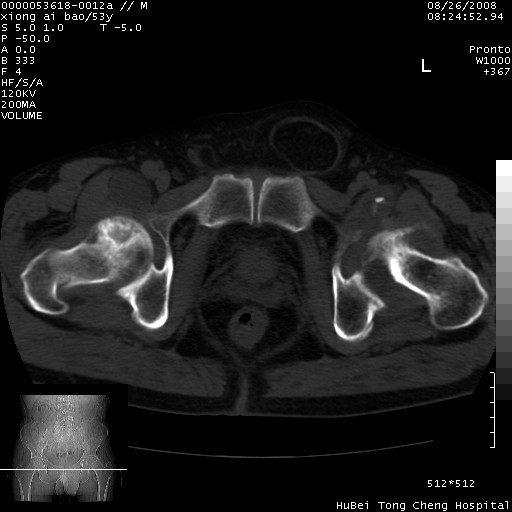

标题: CT15583:M,53Y。请老师指教分析骨盆及其他病变。 [打印本页]

标题: CT15583:M,53Y。请老师指教分析骨盆及其他病变。

股骨头坏死/腹股沟疝。

双侧股骨头无菌坏死,左侧腹股沟斜疝。

非常典型病例,双侧股骨头坏死伴双髋关节周围软组织肿胀,左腹股沟疝。

双侧股骨头坏死伴双髋关节周围软组织肿胀,左腹股沟疝。

双侧骨股头无菌性坏死,左侧腹股沟疝

双侧髋关节肿胀明显,感觉还不能排除结核。

考虑双侧髋关节结核,左侧腹股沟疝